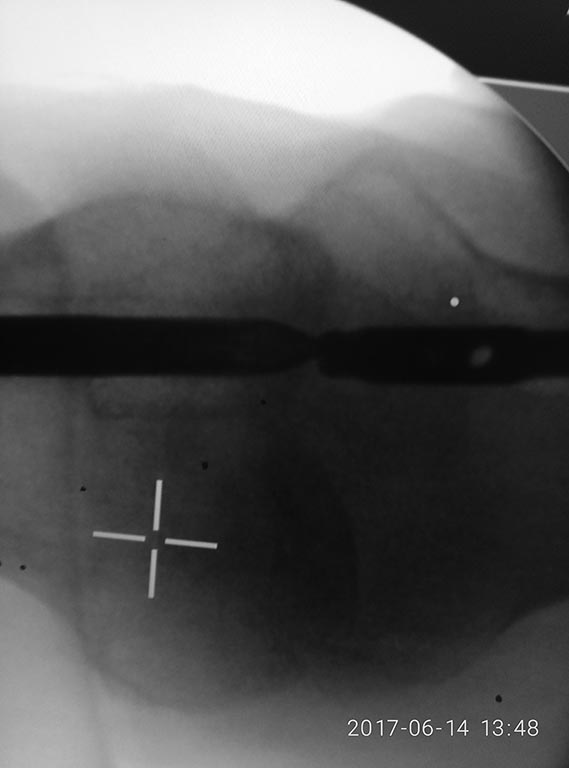

Доброе утро коллеги!фикшен с бедра удалили, сидел очень плотно.

На ортопедическом столе уложили, ногу согнули, как на ретроградное бедро, артротомия, релиз 4-главой, увеличили обьем движений. Далее попытка выбить плечевым, голенным штифтом не сильно имела успех. Стоял на своем. Проксимально по направителю рассверлили канал развертками 11,12. В итоге взяли 11 фемор санатметал, несколько ударов, и он вылетел из бедра!